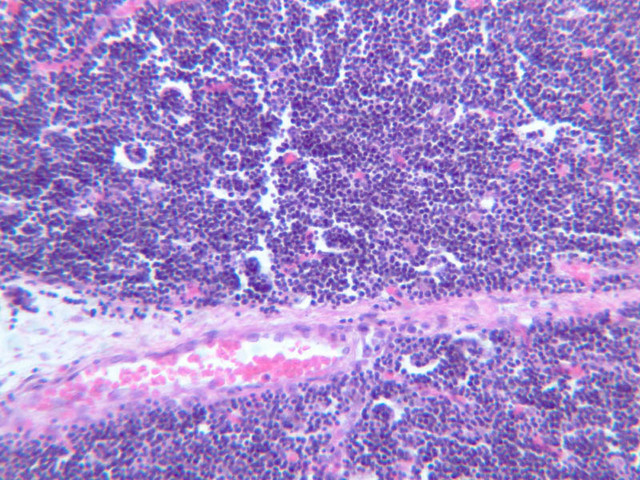

Examine slides A-43 through A-46 (A-43, H&E [2.5x, 10x, 20x]; A-44, H&E [10x, 20x, 40x]; A-46, H&E [2.5x-labeled, 10x, 20x-labeled, 40x]). Slides A-44 and [[http://www.medicalhistology.us/wiki/bin/viewfile/Main/ThymusImages?rev=1;filename=a45_hassall_corpuscle_medulla_infant_thymus_2x.jpg][A- 45]] are from infants and slide A-46 is from a young adolescent. Compare slide A-43 (adult thymus) to slide A-44 (infant thymus). First hold the slides up to the light and observe by eye that there is an increase in the amount of CT (and fat) that infiltrates the tissue with age. Now observe the differences in the appearance of the tissue at the microscopic level. Like the lymph node and spleen, the thymus is encapsulated, and the capsular connective tissue penetrates into the lymphoid tissue dividing it into compartments. But only the thymus appears lobulated. Each lobule is divided into a darker staining peripheral cortex and a lighter staining medulla. Diagnostic of the thymus are Hassall's corpuscles (A-45 [2.5x, 10x, 20x, 40x-labeled]). These are concentrically layered, eosinophilic structures found in the medulla.

Examine a section of young thymus (slides A-44, A-45). Note that it is surrounded by a thin CT capsule. Trabeculae from the capsule pass into the organ to divide the thymus incompletely into lobes (separated by thick trabeculae) and lobules (separated by thinner trabeculae). Notice that the lobules and lobes join centrally, making the parenchyma of the organ continuous throughout. Each lobule shows an outer, cortical region, densely packed with cells that are mostly lymphocytes, and a core or medullary region containing fewer cells. Lymphoid nodules with their germinal centers are absent from the thymus because it has no afferent lymphatics, i.e. this organ does not filter lymph. Examine the cortex and find large and small lymphocytes (A-44, H&E [2.5x, 10x, 20x, 40x] [2.5x, 10x, 20x, 40x]; A-45, H&E [10x, 20x, 40x] [2.5x, 10x, 20x, 40x] [2.5x, 10x, 20x, 40x]). Look for mitotic figures in the thymic cortex; these are lymphoblasts. Also try to discern large cells with acidophilic cytoplasm and large nuclei interspersed among the lymphocytes. These are the epithelioreticular cells. Now look at the medullary region where lymphocytes are sparser (A-44, H&E [10x, 20x, 40x]; A-45, H&E [2.5x, 10x, 20x, 40x-labeled] [10x, 20x, 40x]). Epithelioreticular cells are more readily apparent. Unlike the reticular cells in other lymphatic organs which are of mesenchymal descent, these reticular cells arise from epithelium of the pharyngeal pouches. Like other epithelial cells, thymic reticular cells are joined by desmosomes. In the thymus, the epithelioreticular cells form a cellular reticulum that supports the thymocytes.

Scattered randomly in the medullary tissue are acidophilic structures whose cells are concentrically arranged around an amorphous core. These are the thymic or Hassall's corpuscles. Hassall's corpuscles vary in size and appearance and are comprised of degenerated reticular cells that contain keratohyalin granules and keratin. No known function has been assigned to them.